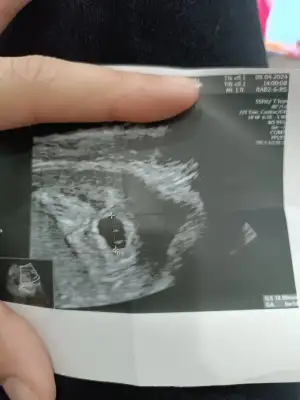

Kızlar yolk sac ne zaman gözükür diye dün sormuştum bir cevap alamamıştım bugün 5+0 kese içinde karından ultrason ile yolk sacı gördük 6. Haftaya kadar görememe olabiliyormuş bilginiz olsun merh

Merhaba ultrason görüntüsü var mı acaba

Eklentiler

• IMG_20240409_120421.webp

IMG_20240409_120421.webp

67 KB · Görüntüleme: 91